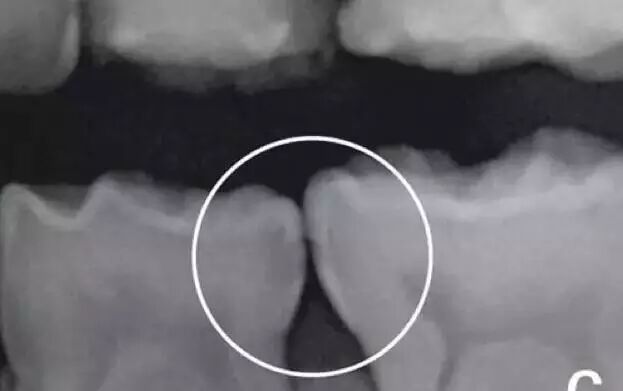

牙齿的邻面龋

邻面龋发生在两颗牙齿的接触点上,牙刷刷不到的位置(牙线可以清除这里),如果没有使用牙线习惯则会容易发生。

邻面龋比咬合面龋更难发现,早期龋没有感觉,一般都是定期拍X光片时才被发现。进展下去会有表面缺损,这时候用牙线会让牙线分丝,断裂,再下去会出现吃东西塞牙、敏感、疼痛。